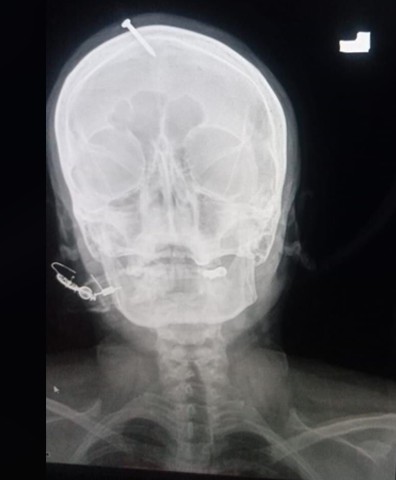

Pákistánská policie pátrá po „léčiteli“, který zatloukl ženě hřebík do hlavy

Pákistánská policie pátrá po muži, který těhotné ženě zatloukl hřebík do hlavy. Podle dotyčné se muž vydával za léčitele a sliboval, že jí úkon zajistí narození chlapce.

Žena se nejprve snažila pět centimetrů dlouhý hřebík vytáhnout kleštěmi, což se jí nepodařilo. Následně přišla do nemocnici v Péšávaru, kde podstoupila operaci. Nejprve lékařům tvrdila, že si zranění přivodila sama. Později ale přiznala, že se svěřila do rukou údajného léčitele, který sliboval, že jí zajistí narození chlapce. Žena byla podle lékaře Haidera Chána při příjezdu do nemocnice plně při vědomí, trpěla ale obrovskými bolestmi.

Případ začala policie vyšetřovat až poté, co se rentgenové snímky objevily na internetu. Vyšetřování komplikuje skutečnost, že žena po odstranění hřebíku nemocnici opustila. Policie několik dní vyslýchala zaměstnance nemocnice a podle Ahsana zjišťuje, proč incident policii nenahlásili, když se jim žena svěřila do péče. Policisté se ji nyní snaží vypátrat v naději, že jí pomůže identifikovat pachatele. „Brzy toho čaroděje dopadneme,“ věří šéf péšávarské policie Abbás Ahsan.